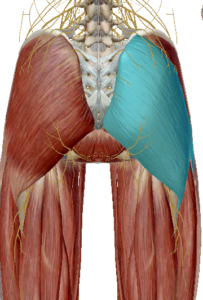

(2) 대둔근

대군근은 장골과 엉치뼈를 지나며 대퇴골에 연결되어 있습니다.

고관절의 신전과 외회전을 발생시킵니다.

(3) 중둔근과 소둔근

중둔근은 고관절 측면 안정성에 중요한 근육입니다.

수축 시 고관절 외전과 섬유의 위치에 따라 내회전과 외회전도 관여한다고 합니다.

소둔근도 중둔근과 같이 고관절 측면 안정성에

중요한 역할을 합니다.

고관절 외전을 발생시키며 고관절 앞쪽에 연결되어 있어 고관절 굴곡과 내회전을 발생합니다.